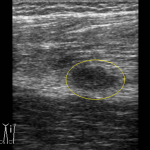

こちらの患者さんは40代男性で、野球をしていて受傷しました。野球は経験者です。

ただ今回は結構深い所の筋肉が損傷しており、固定も難しいかもしれましせんが、包帯ではなく強力なバンテージにて固定しました。

エコーで観たとこと皮膚から5cm位下なので超音波もギリギリ届くかという所です。